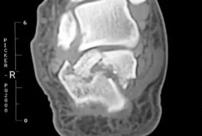

跟骨骨折冠状面影像

当跌倒后出现足后跟剧烈疼痛,局部肿胀及瘀斑明显,跟骨压痛,无法下地行走,应高度怀疑跟骨骨折,要马上到医院确诊(拍X光片,跟骨正侧位+轴位片)。对于严重的粉碎性或者波及关节面的骨折,最好还要做个CT,指导具体手术方案。

足部的骨骼结构复杂,这使跟骨骨折的复位,变得有难度。首先跟骨与3个关节面连接,包括前距关节面,中距关节面,和后距关节面;这三个关节面分别与前跟、中跟、后跟组合成了距下关节。再者,跟骨与多条韧带相连,包括跟腓韧带等。